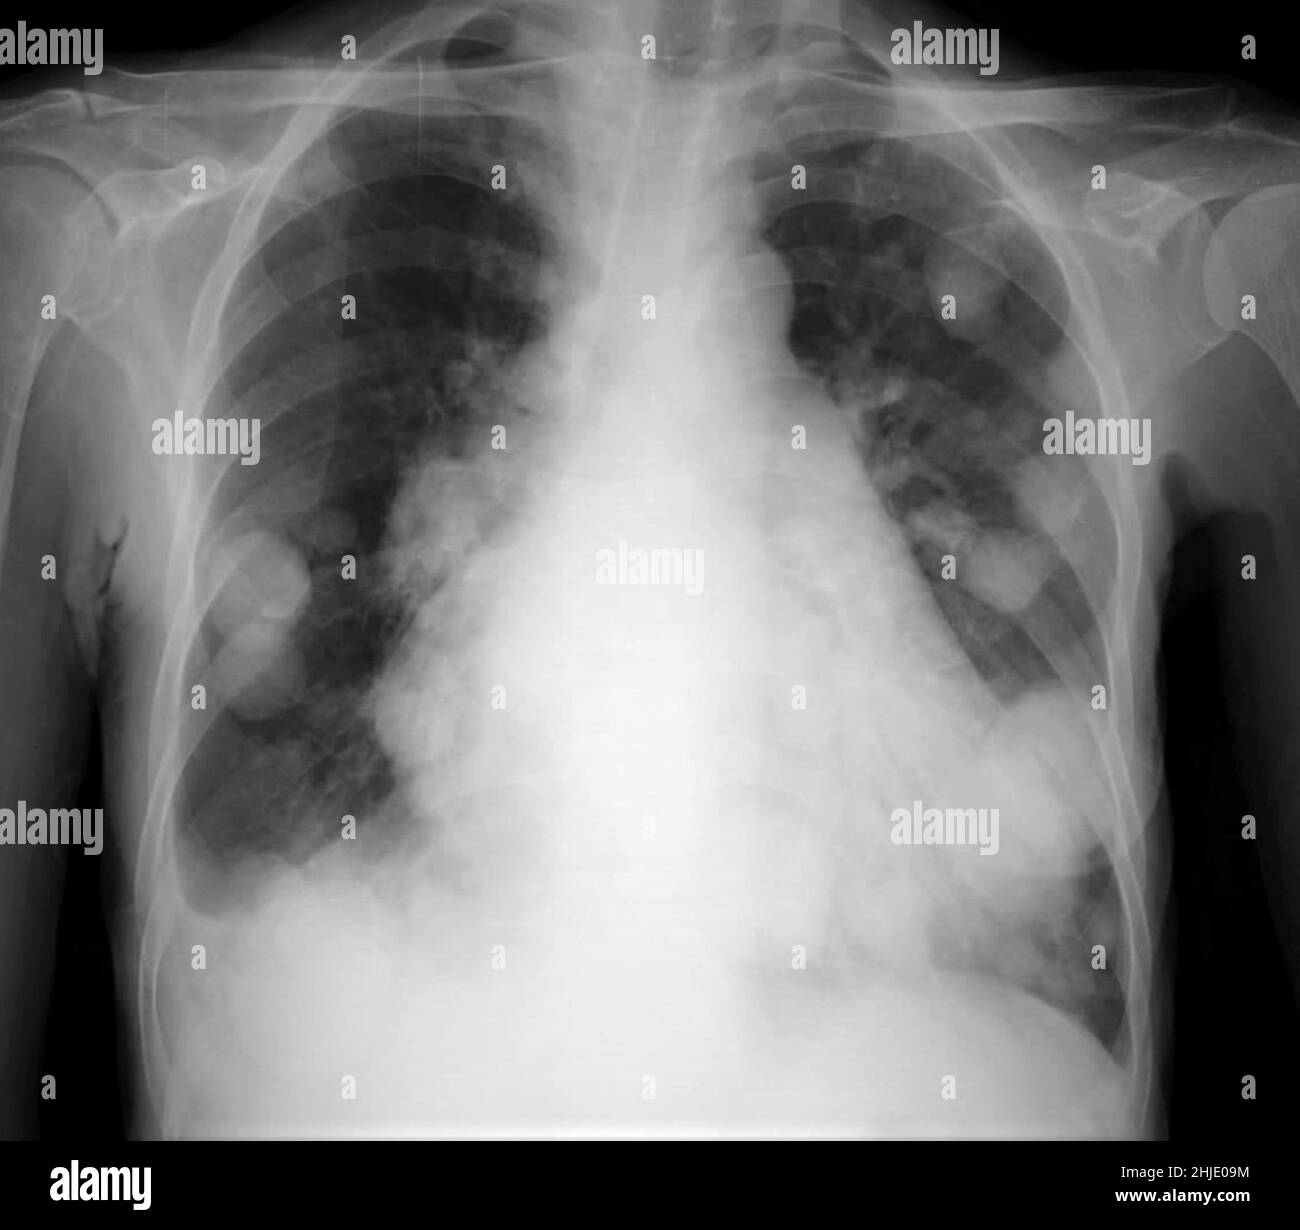

Cannon Balls X Ray . Atypical features include consolidation ,. The most obvious finding is that of numerous bilateral round hyperdensities of variable sizes of the pulmonary. — larger nodules and masses may be termed cannonball metastases.

Atypical features include consolidation ,. — larger nodules and masses may be termed cannonball metastases. The most obvious finding is that of numerous bilateral round hyperdensities of variable sizes of the pulmonary.

Cannon Balls X Ray — larger nodules and masses may be termed cannonball metastases. Atypical features include consolidation ,. The most obvious finding is that of numerous bilateral round hyperdensities of variable sizes of the pulmonary. — larger nodules and masses may be termed cannonball metastases.